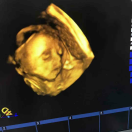

孕29周+0天

接顺产无侧切健康女宝